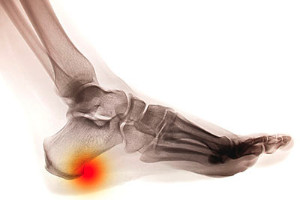

How Do Heel Spurs Form?

Heel spurs are bony protrusions that form on the heel bone due to calcium deposits.  These deposits tend to form over time and may be a result of a ligament that is connected to the heel bone being frequently overstretched and ultimately torn.  The most common issue that leads to heel spurs is plantar fasciitis which occurs when the band of tissues running along the bottom of the foot get injured and inflamed.  In fact, plantar fasciitis is the cause for around half of all heel spurs.  Heel spurs are often indicated by pain, tenderness and swelling that can make walking difficult.  If you are struggling with heel pain, it may be serious, and consulting with a podiatrist is recommended.

Heel spurs are formed by calcium deposits on the back of the foot where the heel is. This can also be caused by small fragments of bone breaking off one section of the foot, attaching onto the back of the foot. Heel spurs can also be bone growth on the back of the foot and may grow in the direction of the arch of the foot.

The pain associated with spurs is often because of weight placed on the feet. When someone is walking, their entire weight is concentrated on the feet. Bone spurs then have the tendency to affect other bones and tissues around the foot. As the pain continues, the feet will become tender and sensitive over time.